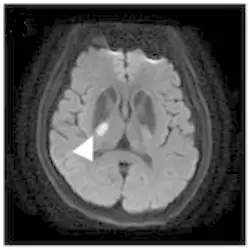

- 影像類型:這是一張腦部 MRI 的軸切面(Axial view),從顯影的高訊號(亮白)病灶來看,極可能為擴散權重影像(DWI),顯示急性的缺血性中風。

- 解剖構造辨識:

- 左右定位:放射科影像慣例為「左圖右腦」,即圖片左側代表病人的右腦。題目敘述病人為「左側」下肢無力,故病灶應位於「右側」大腦半球,與影像相符。

- 核心構造:

- 視丘(Thalamus):位於影像中央偏內側的灰質核團,緊鄰第三腦室。

- 豆狀核(Lentiform Nucleus):位於外側的灰質結構。

- 內囊(Internal Capsule):位於視丘與豆狀核之間的 V 字形白質纖維束。

- 病灶位置(箭頭處):白色箭頭所指的高訊號病灶位於右側大腦半球深部。它清楚地坐落在視丘(內側)與豆狀核(外側)之間的白質帶,且位於該 V 字形結構的後臂。此區域即為內囊後腳(Posterior limb of internal capsule, PLIC)。